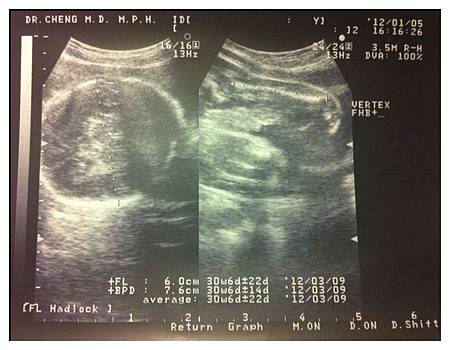

@今天P陪我去產檢,這也是他第一次來到台灣的婦產科,也算是個新體驗吧!!去到診所,感覺大家都在看他,不知道是因為他不是台灣人?還是去產檢的剛好都沒有先生陪!! 醫生好厲害,問了P會不會說中文,知道不太會之後就全程用英文跟他解釋超音波(這個嚇到我)~檢查結果醫生說baby比平均值大了兩週~所以要減少澱粉及糖類的攝取!!!不過一檢查完經過綠逗薏人又忍不住的馬上來碗甜的,整個就把醫生的話當耳邊風…可是我下星期就要回去了,現在不好好把握吃還有什麼時間可以吃啦!!!